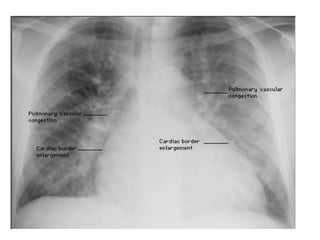

Figure 11.35 Chest X-ray in acute left ventricular failure:

the patient had severe pulmonary oedema caused by acute

myocardial infarction. The heart is not yet enlarged, but there

is prominent alveolar pulmonary oedema in a perihilar (‘bat’s-

wing’) distribution. Note the bilateral pleural effusions.